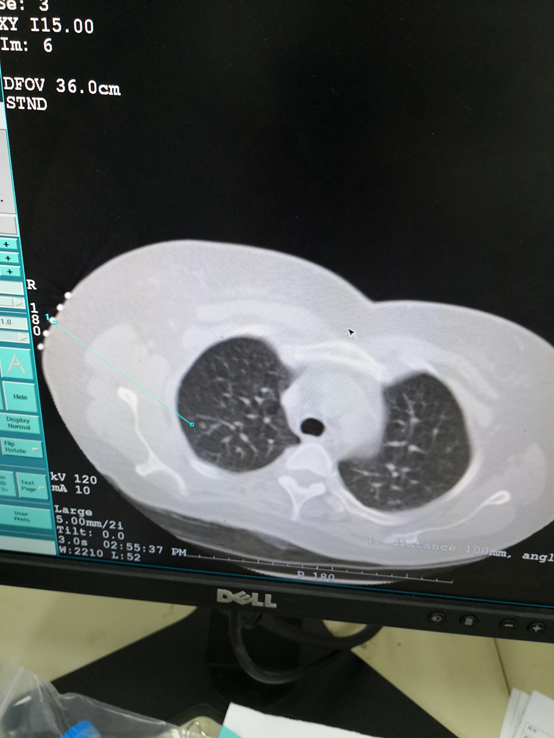

图文教你看懂恶性肺结节的ct表现_肺部结节_相关检查_就诊指导 - 好

图片尺寸3648x2736